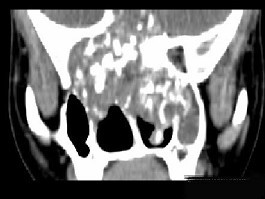

男性,28岁,因鼻塞、头痛1年余,鼻窦CT扫描如图所示,请选择正确的描述与结论()

A.双侧上颌窦、筛窦、鼻腔及蝶窦内见软组织肿块影

B.肿块内密度不均,有较多致密钙化影

C.窦壁及颅底骨质破坏

D.考虑鼻窦骨瘤

E.考虑为鼻窦软骨瘤

[多选题]男,28岁,因鼻塞、头痛1年余,鼻窦CT扫描如图所示,正确的描述或诊断是()A.双侧上颌窦、筛窦、鼻腔及蝶窦内见软组织肿块影B.肿块内密度不均,有较多

[多选题]男,28岁,因鼻塞、头痛1年余,鼻窦CT扫描如图所示,正确的描述或诊断是()A.双侧上颌窦、筛窦、鼻腔及蝶窦内见软组织肿块影B.肿块内密度不均,有较多

[多选题]男,28岁,因鼻塞、头痛1年余,鼻窦CT扫描如图所示,正确的描述或诊断是()A.双侧上颌窦、筛窦、鼻腔及蝶窦内见软组织肿块影B.肿块内密度不均,有较多

[多选题] 男性,28岁,因鼻塞、头痛1年余,鼻窦CT扫描如图所示,请选择正确的描述与结论()。A . 双侧上颌窦、筛窦、鼻腔及蝶窦内见软组织肿块影B . 肿块内密度不均,有较多致密钙化影C . 窦壁及颅底骨质破坏D . 考虑鼻窦骨瘤E . 考虑为鼻窦软骨瘤

[多选题] 男性,28岁,因鼻塞、头痛1年余,鼻窦CT扫描如图所示,请选择正确的描述与结论()A .双侧上颌窦、筛窦、鼻腔及蝶窦内见软组织肿块影B .肿块内密度不均,有较多致密钙化影C .窦壁及颅底骨质破坏D .考虑鼻窦骨瘤E .考虑为鼻窦软骨瘤